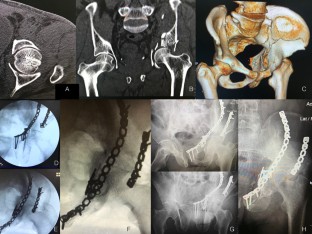

Fig. 3